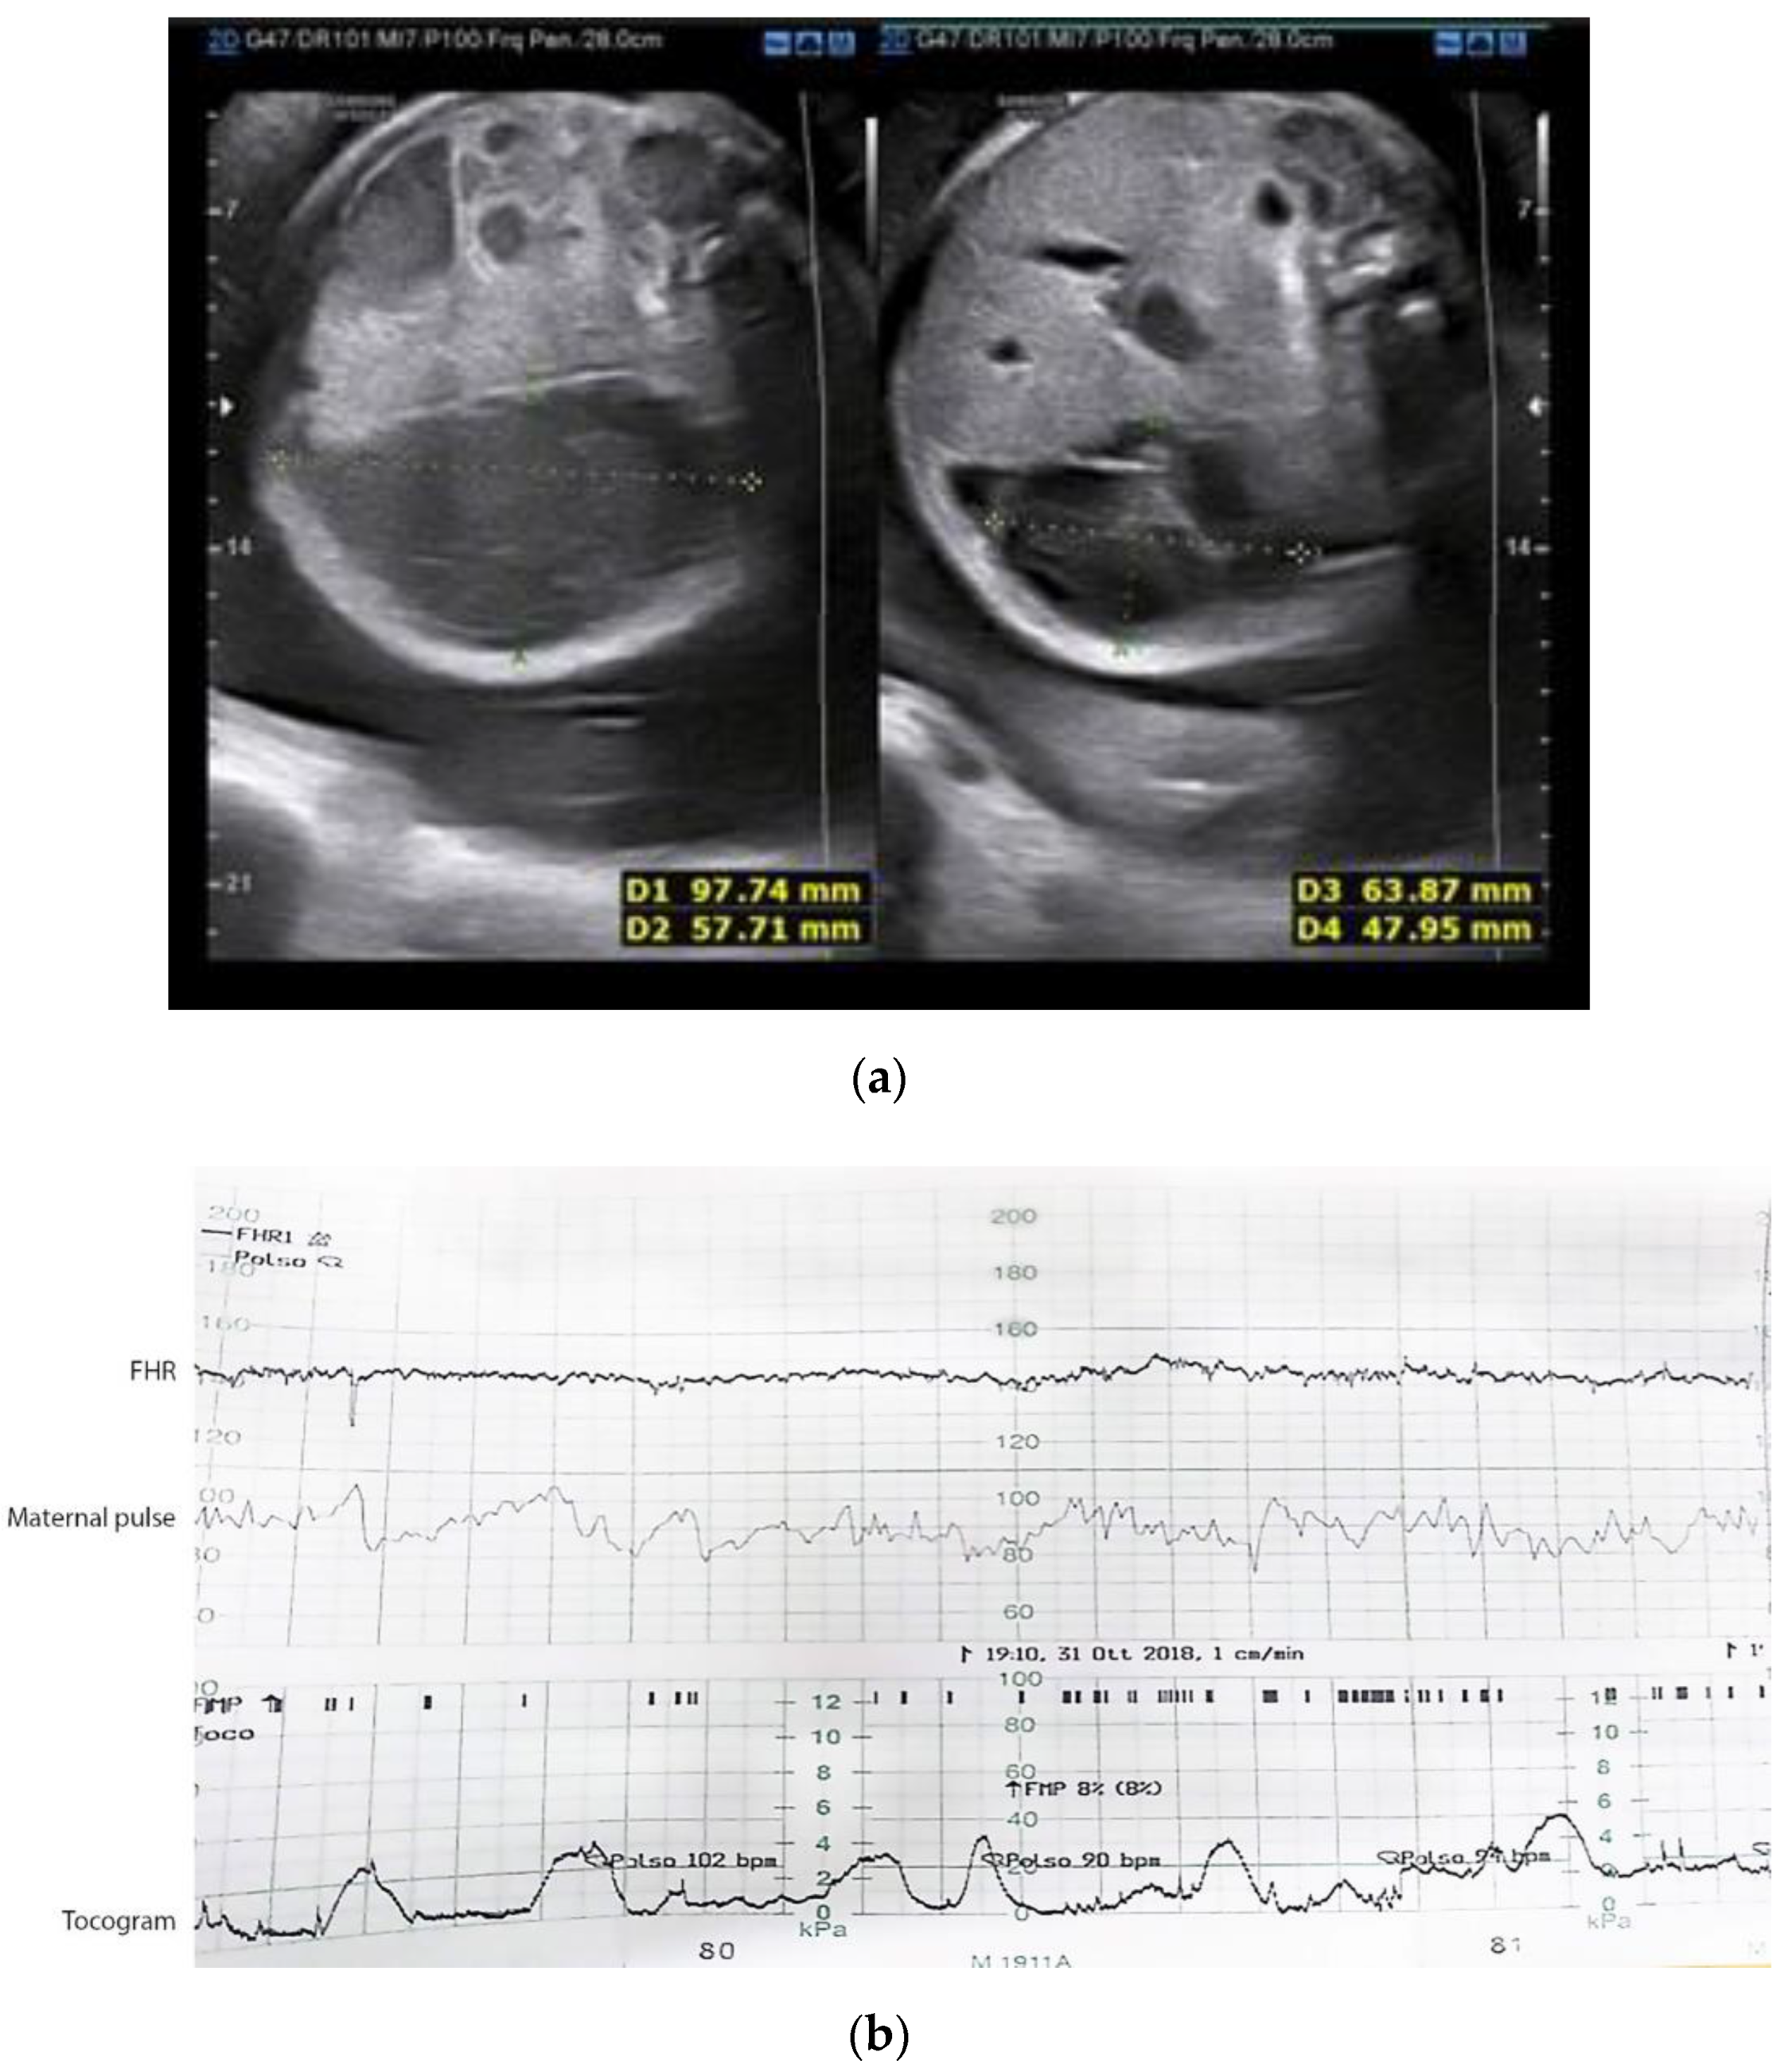

2.1. Case 1

2.2. Case 2